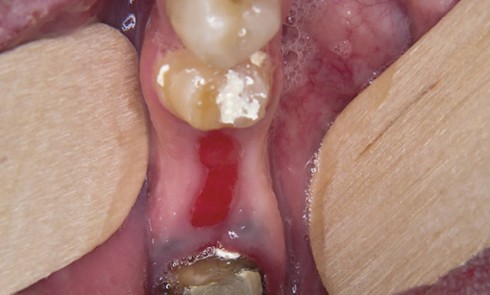

Article réservé à nos abonnés Pathologies de la muqueuse buccale et douleur aiguë

Les pathologies de la muqueuse buccale sont des pathologies aiguës ou chroniques qui s’accompagnent, pour certaines d’entre elles, de douleurs...